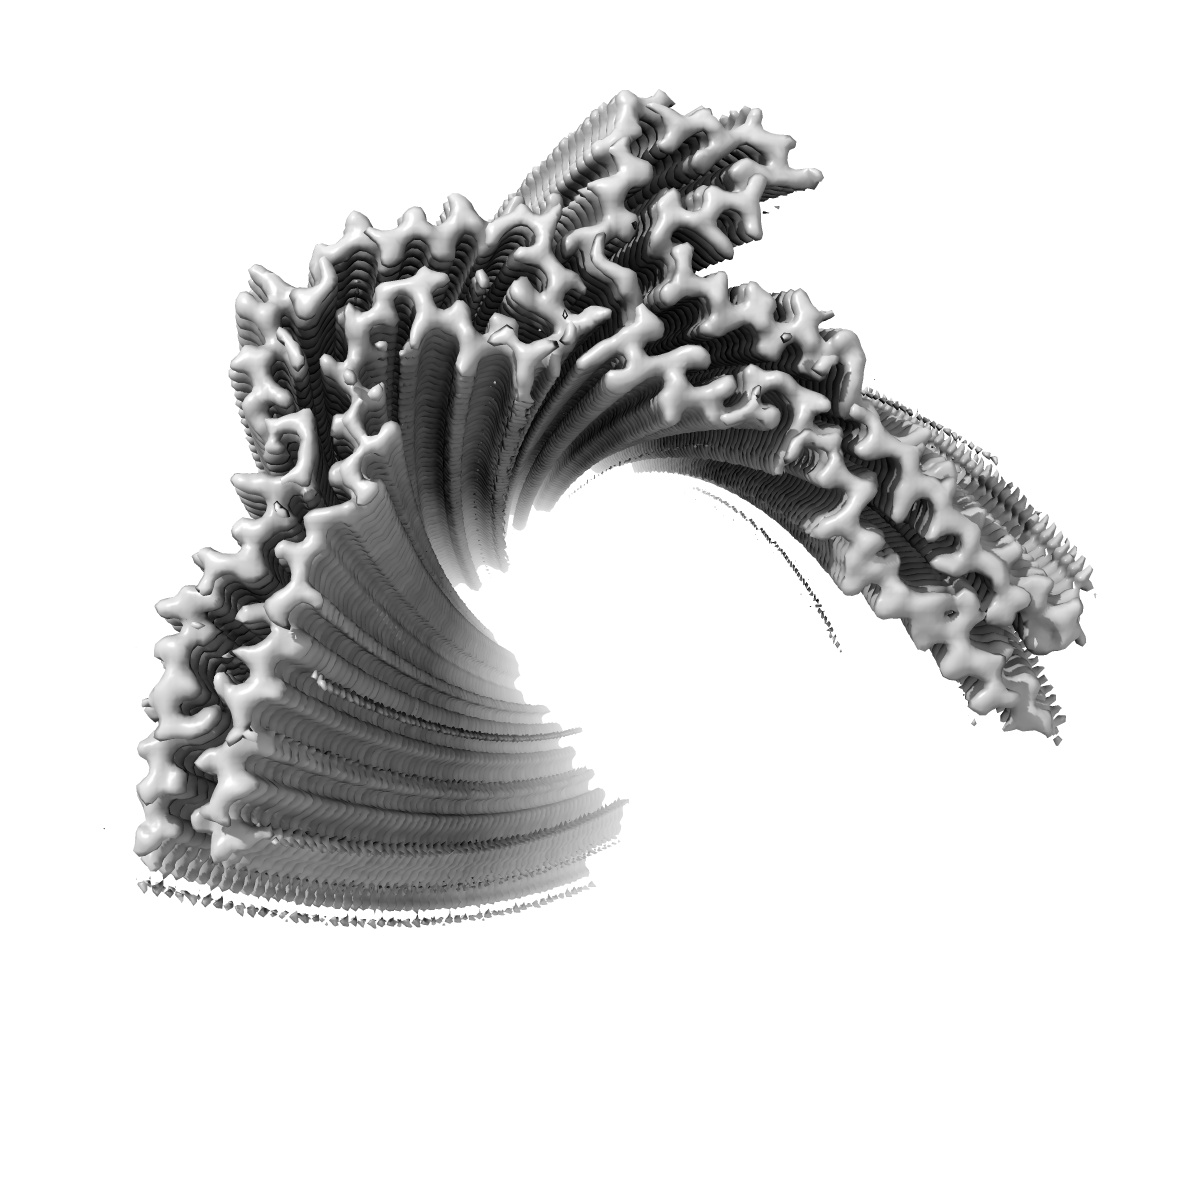

Tau - AD-MIA6 (tau intermediate amyloid)

Helical reconstruction

2.82 Å

Deposition Authors: Lovestam S, Li D , Scheres SHW , Goedert M

Disease-specific tau filaments assemble via polymorphic intermediates.

Lovestam S, Li D , Wagstaff JL, Kotecha A , Kimanius D, McLaughlin SH , Murzin AG, Freund SMV , Goedert M , Scheres SHW

(2024) Nature , 625 , 119 - 125